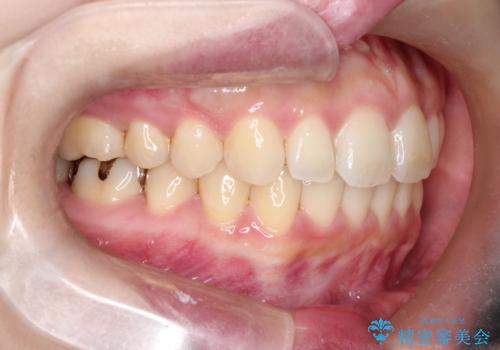

【インビザライン】前歯が出てるのを治したい

- 前歯の凸凹と前突を主訴に来院されました。

インビザラインにて治療をおこない、歯並びを改善することができました。